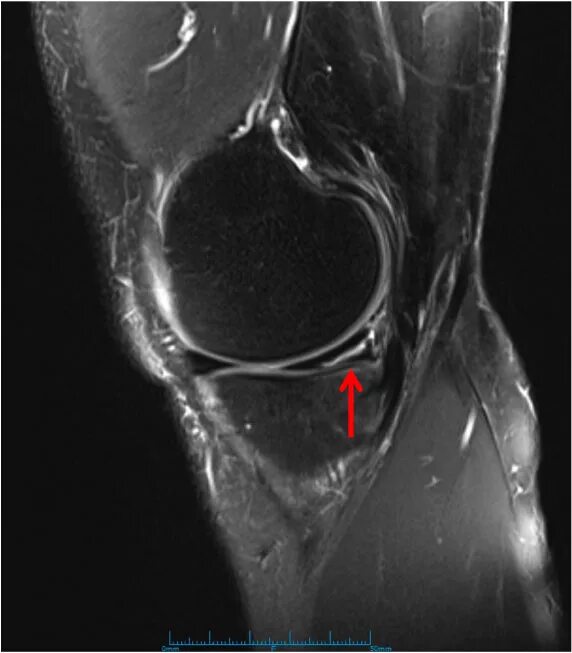

Повреждение мениска мрт